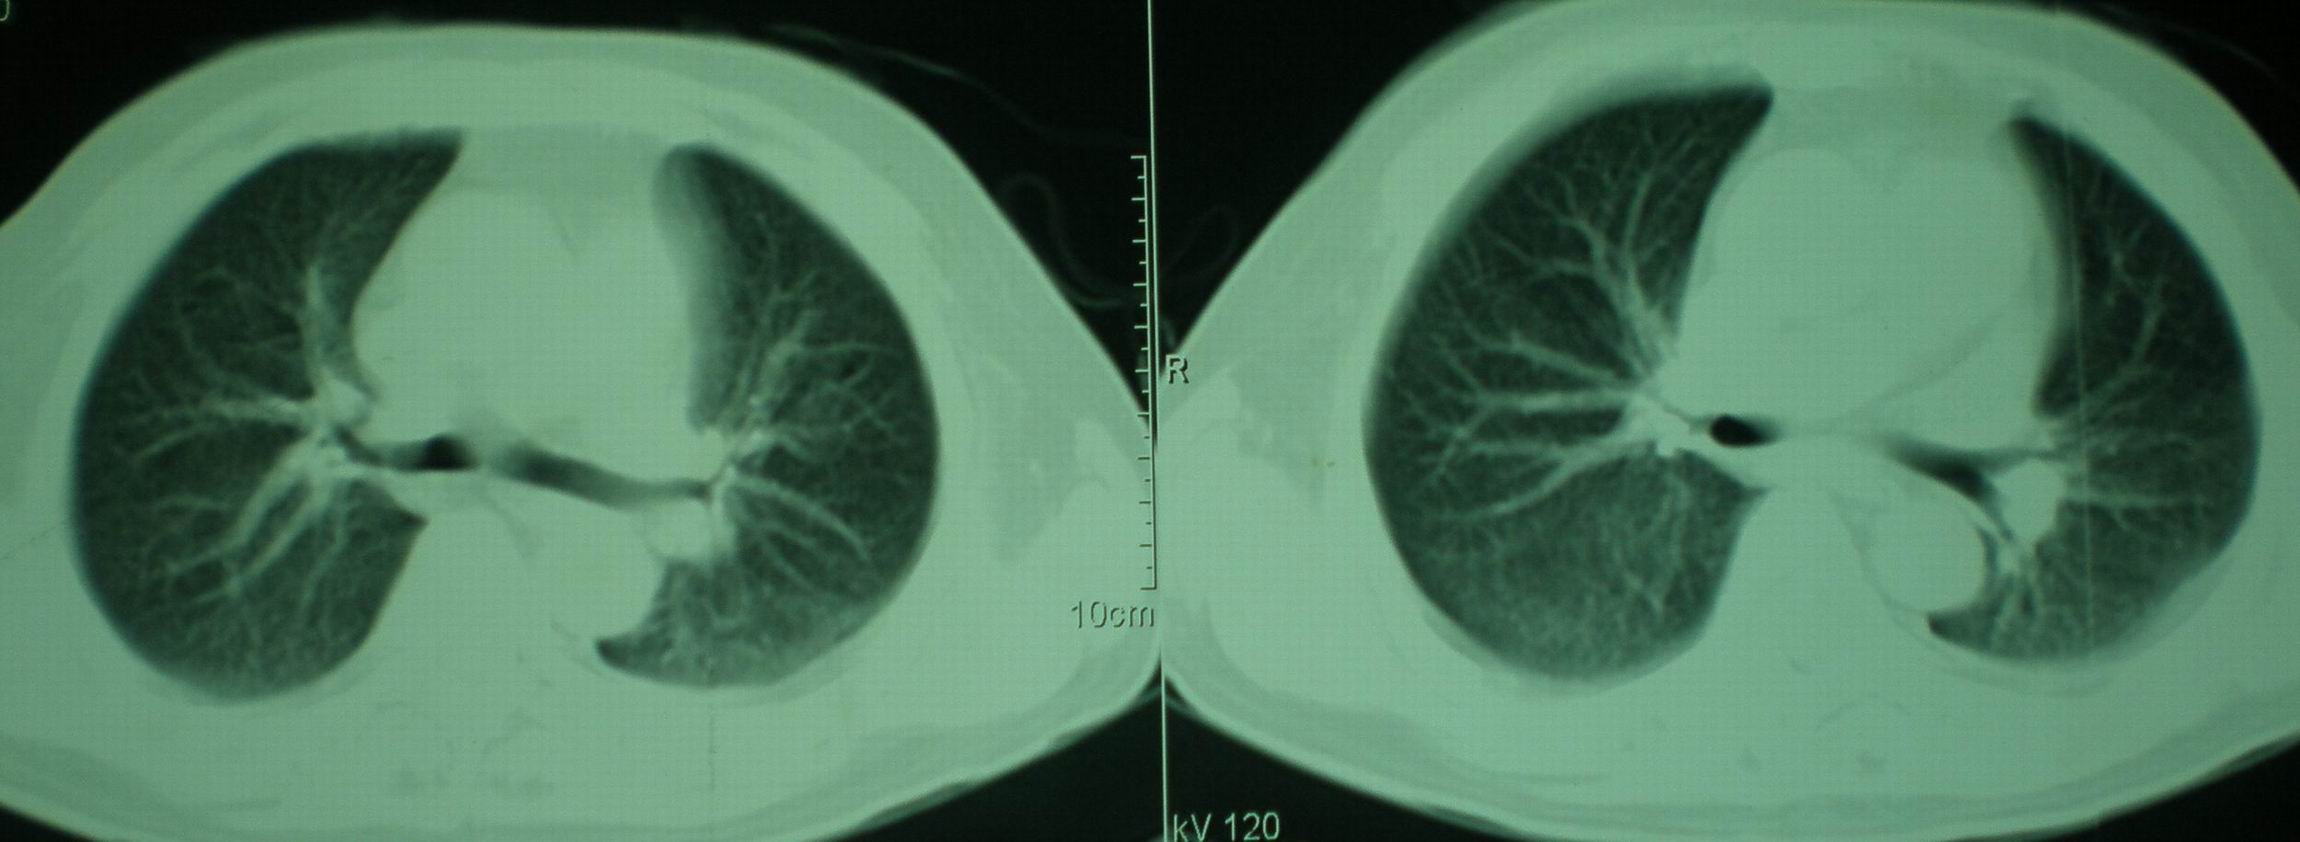

2008年9月8日ct片:

机遇性感染!不除外急性肺水肿!

急性心衰所致肺水肿,双侧胸腔积液,少量心包积液可能?结合临床及其它检查.

我仔细看了下病人的出院小结,当时情况危急,诊断里有1型呼衰。心包周围的是脂肪密度。结合三次ct扫描的图象分析,个人认为:1、病人目前肺部病灶基本消失,双侧胸腔内少量积液,抗结核治疗才一个多月,就算是结核,抗结核治疗有效果,为何效果如此好,一点纤维灶的痕迹都没有呢,再就是患者做过气管镜检查及活检、痰检均未找到结核的证据。所以不支持结核的诊断。

急性呼吸窘迫综合征,肺水肿,与激素减量太快有关.双侧胸腔积液.

结合药物使用后急性症状,考虑肺水肿,胸腔积液。